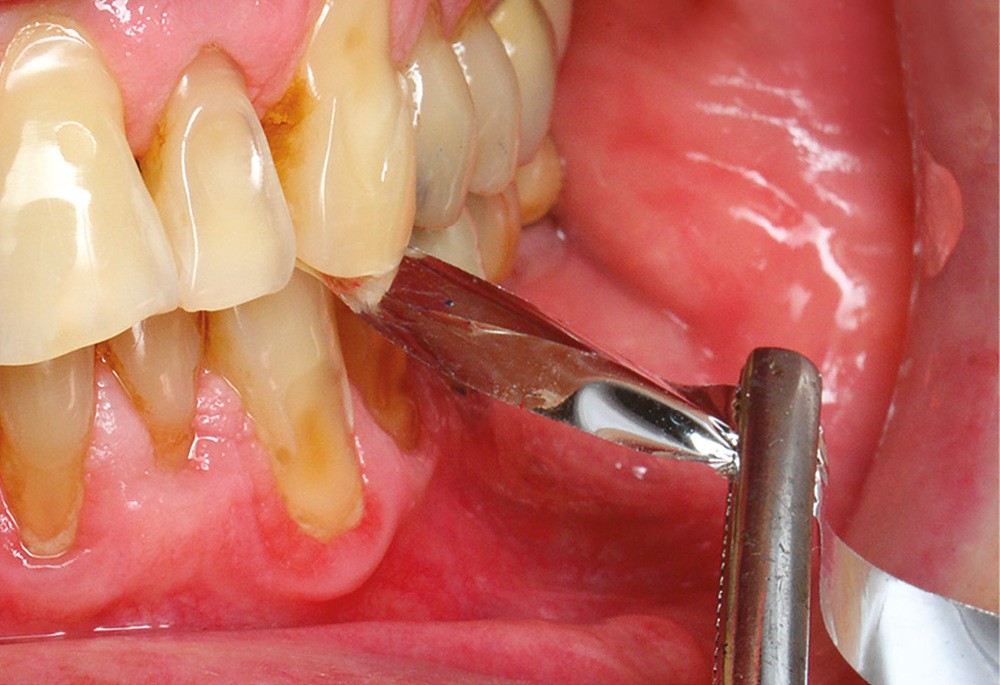

Lorsqu’il est difficile de sécher correctement les surfaces occlusales, une autre technique décrite consiste à vaseliner le papier à articuler pour mieux marquer les surfaces de contact [1] (fig. 3).